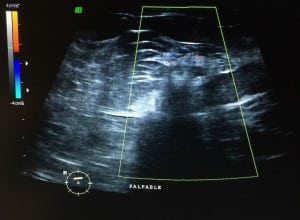

Mastografía: se ve un nódulo de características sospechosas; deciden hacerle más proyecciones para ver mejor el tumor. Le hacen un ultrasonido y encuentran la sig. imagen:

Caso 3.